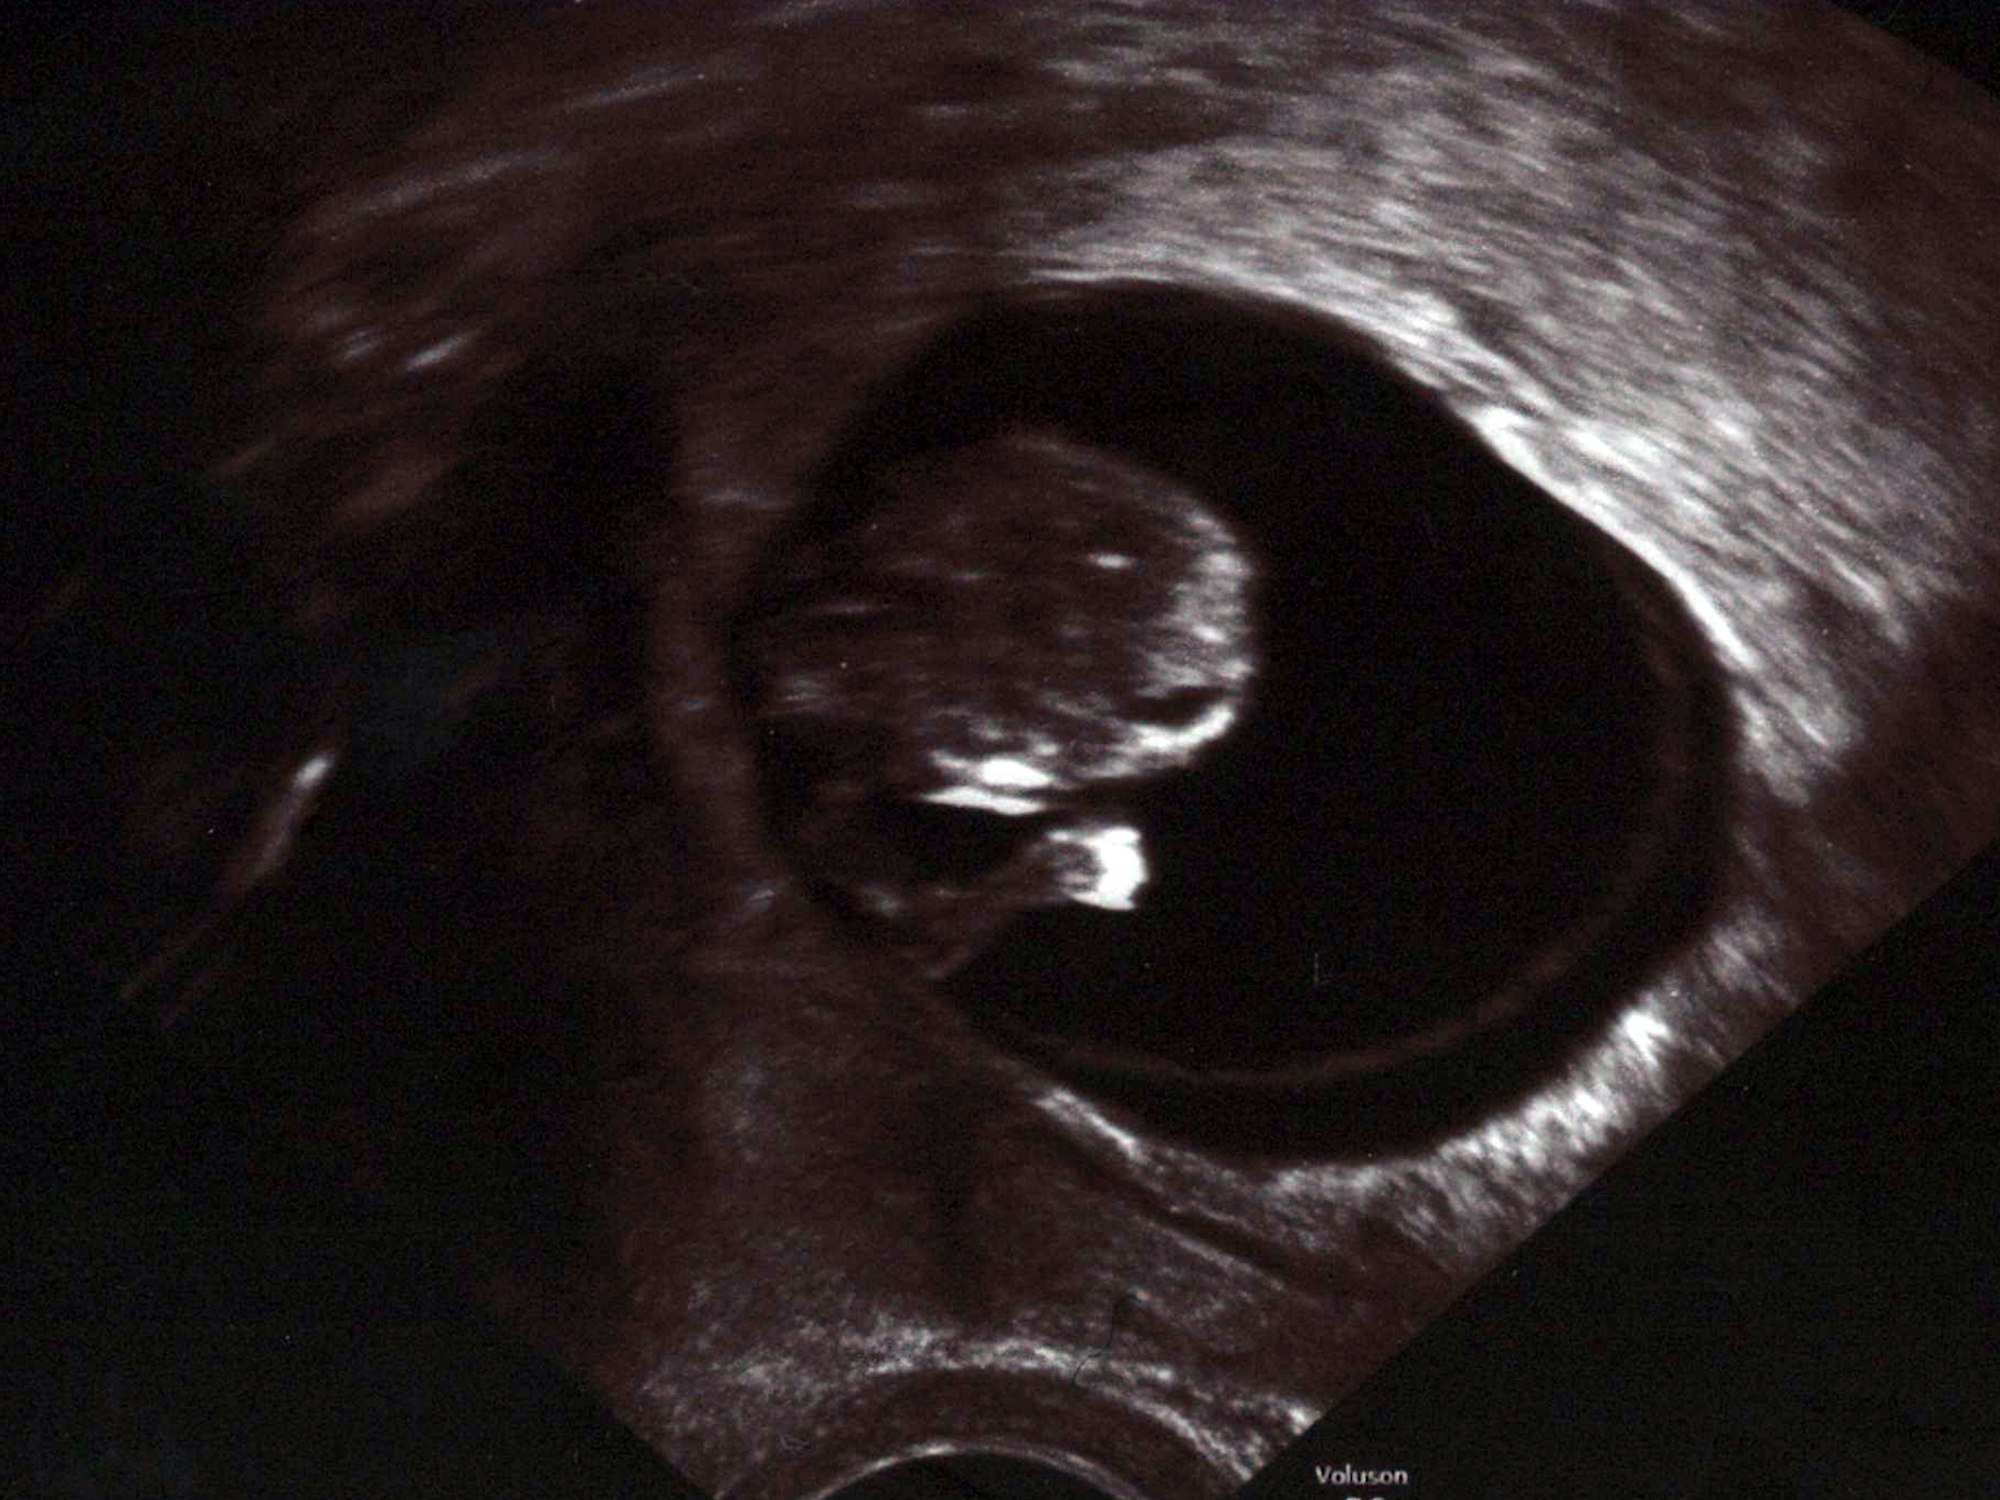

Schon in der 10. Woche ist das Ungeborene deutlich zu erkennen und man kann seinen Herzschlag auf dem Ultraschallgerät sehen.

Copyright: dpa-tmn